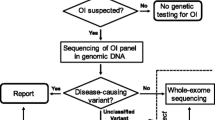

OI should be suspected in all children presenting with increased bone fragility, including fractures that occur with little or no trauma. Positive diagnosis is typically made on the basis of personal and familial medical history, physical examination (preferably with a clinician who is familiar with OI), radiography and, in some cases, complementary investigations such as bone densitometry, biochemical tests or DNA-based sequencing. On radiographs, OI has no pathognomonic features, but some of them may be suggestive of the diagnosis. Recent advances in the treatment of OI with biphosphonates have resulted in radiographic findings, of which the physician must be aware. Usually differentiating OI from NAI is not difficult in young children, though the issue is often raised in court in the defence of cases of NAI, but if necessary radiography is very useful for the differential diagnosis.